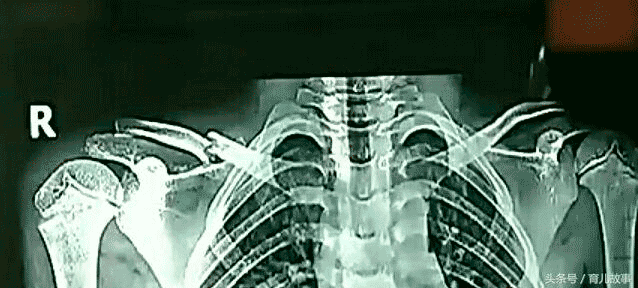

七歲孩子沒帶作業本上學,父母接到電話孩子鎖骨斷成了兩半

年僅七歲的小賀(化名)這天也沒有帶作業本,不僅沒帶作業本鎖骨處還骨折了,問老師是怎么回事的時候老師含糊的告訴家長:沒打孩子,沒罰孩子,就拿教桿指了小賀一下,小賀就不知道怎么的自己倒下了,后來小賀的鎖骨就骨折了。

相關人員表示很好奇呀,于是采訪了與小賀同一個班的孩子。那些孩子說的和老師說的簡直就是兩個版本,小賀的同學說:老師先是打了小賀的手,然后再推了小賀,接著才有后來的事情發生。那小賀的傷情嚴重么?X光顯示小賀的鎖骨已經斷成了兩節,由于小賀太小不能手術,所以只能固定住肩膀讓其慢慢的恢復。